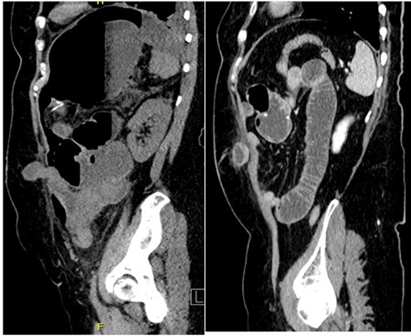

Figure 3: CT scan lateral vision demonstrating trocar site hernia at left upper abdominal quadrantdemonstrating small bowel obstruction.

Left paraumbilicalRight upper quadrant (Figure 3) |

12mm |

Bowel obstruction Omental hernia |

Bowel reduction Omental reduction |